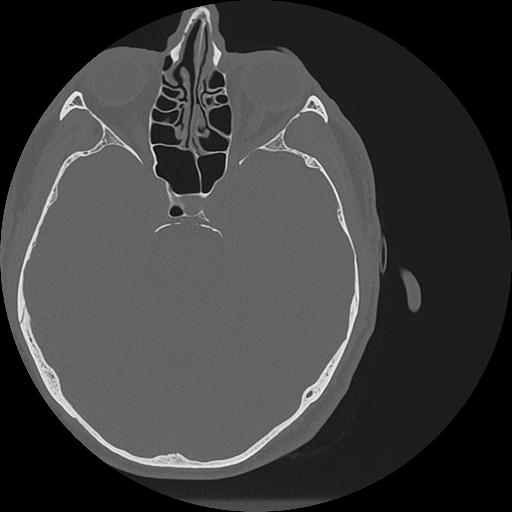

7 HUESO,,Vol,0.5,HUESO,,